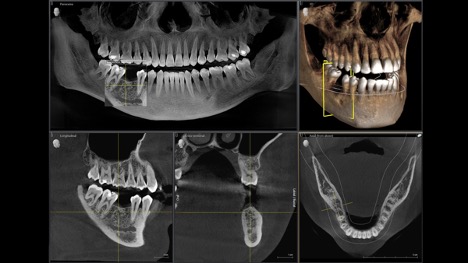

At Jupiter Dentistry, our 3D Cone Beam CT Scan is a cornerstone of our commitment to exceptional dental care. Under the expertise of Dr. Dylan Tagg, this advanced technology delivers safer, more precise, and highly effective diagnostics for dental implants, bone grafting, and other treatments. Serving patients in Jupiter, Tequesta, Palm Beach Gardens, and West Palm Beach, our state-of-the-art scanner ensures unparalleled accuracy for your smile transformation.

- Unmatched Precision: Captures images with accuracy down to 1/100th of a millimeter, allowing Dr. Tagg to measure jawbone volume, density, structure, and shape with pinpoint accuracy.

- Image Processing: The images are combined into a detailed 3D model, which Dr. Tagg can manipulate and segment into half-millimeter sections for precise analysis.